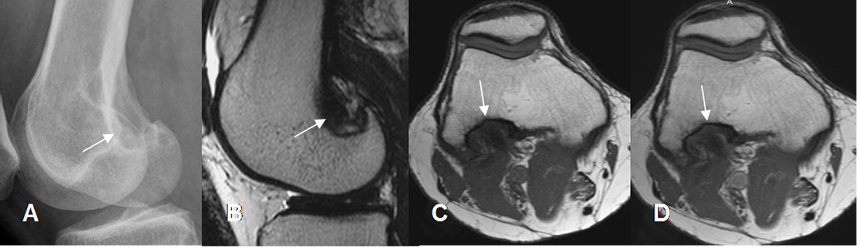

Fig 204. Cambios PostQx.

A: Rx lateral y B: RM sagital en T2. Remodelación en la parte posterior del cóndilo femoral lateral, por el curetaje de un osteoblastoma.

C: RM axial en T1 simple y D: RM axial en T1 con contraste. El defecto óseo está ocupado por tejido blando, sin realce del contraste que sugiera recidiva tumoral.